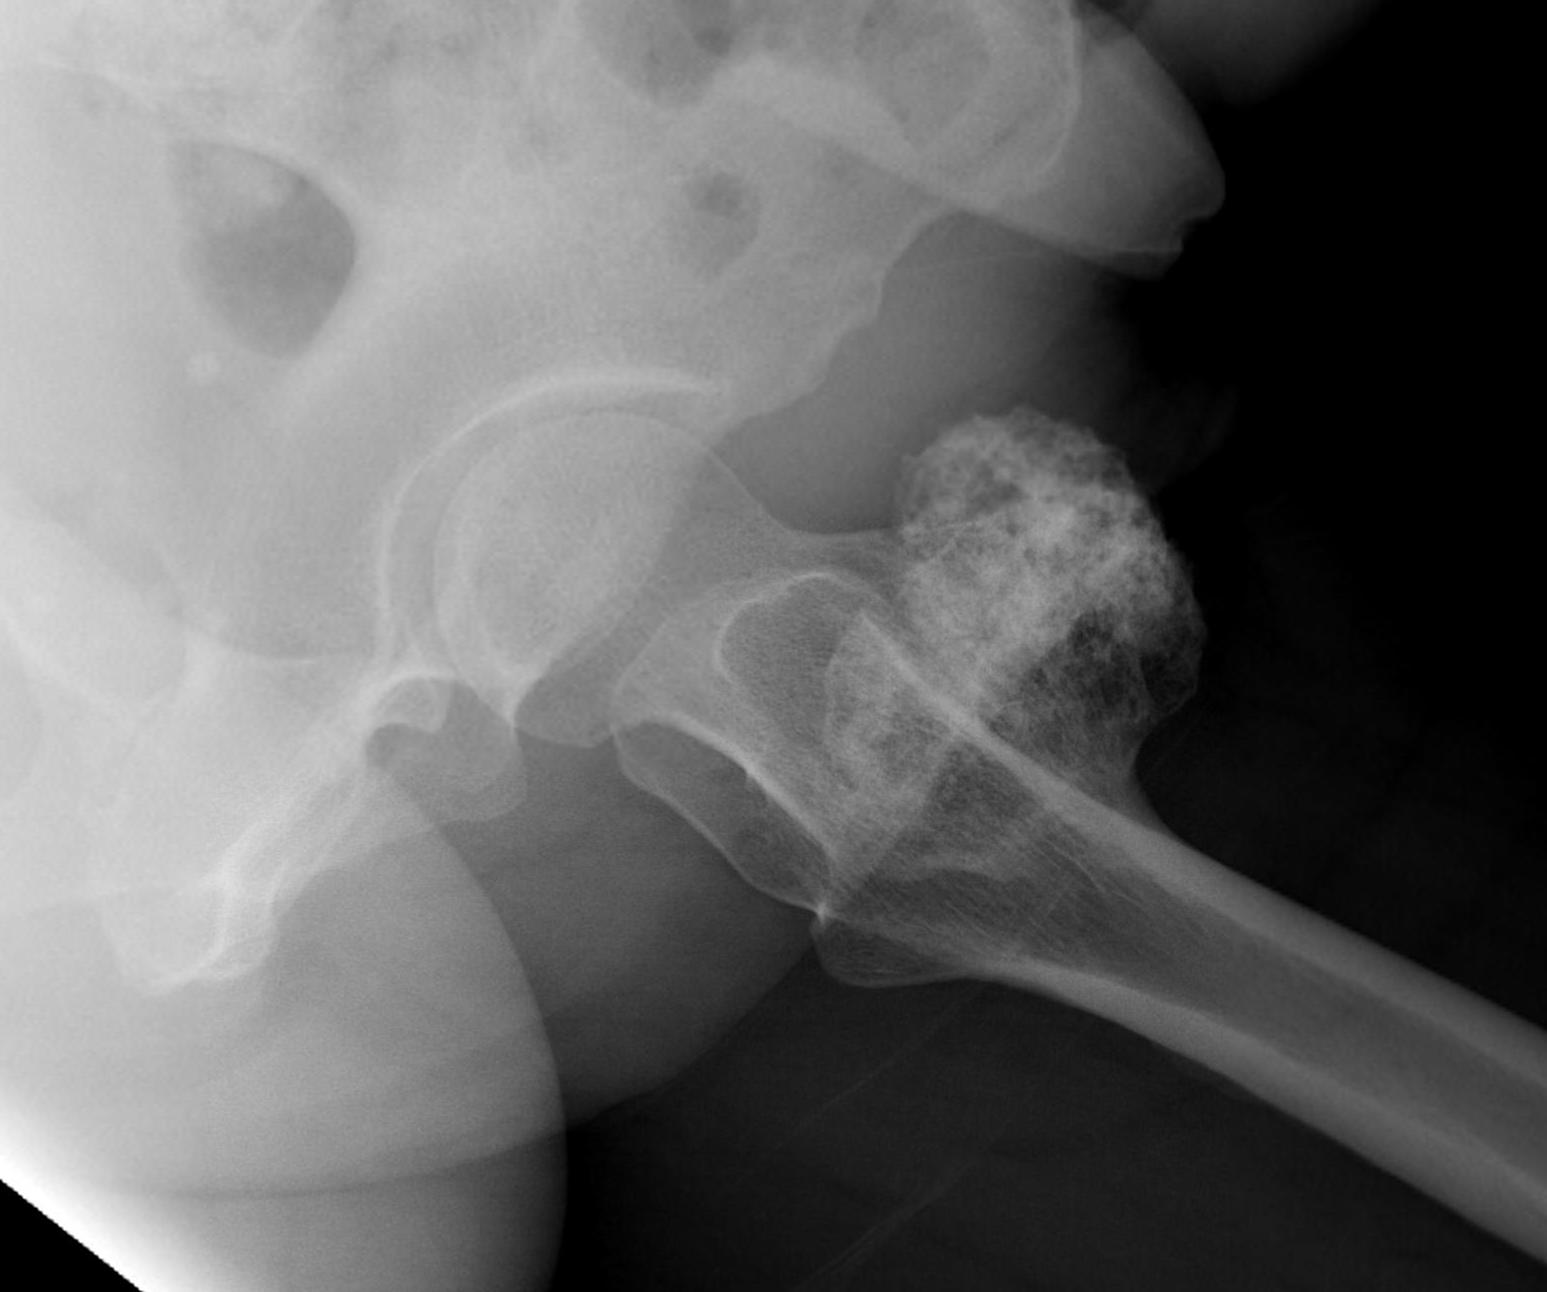

1. Femoral head / neck

- lateral approach

- trans trochanteric

- avoid NV bundle and quadriceps